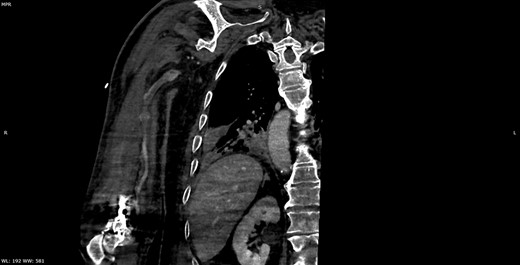

He initially received supportive treatment but clinically deteriorated 48 h post admission, developing hypoxemic respiratory failure. His chest X-ray and computed tomography (CT) of the chest at that time revealed multiple ground glass opacities and areas of consolidation (Fig. 1). He was transferred to the intensive care unit (ICU), where he was intubated, and his treatment was escalated to broad-spectrum antibiotics and hydroxychloroquine. He had been on prophylactic enoxaparin (6000 IU/once daily) since the beginning of his hospital admission. Laboratory results upon ICU transfer are summarized in Table 1. In regard to his coagulation parameters, he had a prolonged activated partial thromboplastin time (aPTT), increased D-dimer and fibrinogen. His platelets were within normal range.

CT of the chest showing bilateral multiple ground glass opacities and areas of consolidation consistent with COVID-19 pneumonia.